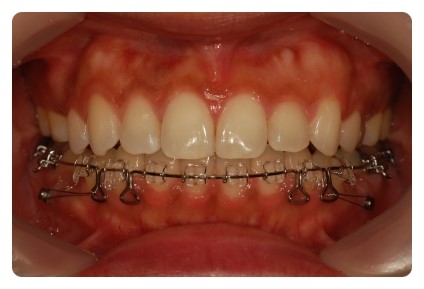

정면사진보니깐 왠지 교정 이제 마무리해도 될것같은데 ~~~ 사실 아직도 발치공간 마니 남앗어요

측면사진도 오랫만에 보니 ~~~ 약간 뻐드러져 ? 잇던 치아가 편평하게 쏙 들어가잇네요

위에 정면사진보시면 지금은 다시 맞아졌어요

난 별로 중심선따위 신경쓰지않을줄 알앗는데 몇달정도 틀어져보니까 장난아니더라구요

거울볼때마다 거슬리고 ;; 중심선 약간 틀어진정도인데 막 턱이 돌아간듯한 자괴감에 빠지며 ;;

근데 다시 돌아와서 다행이에요